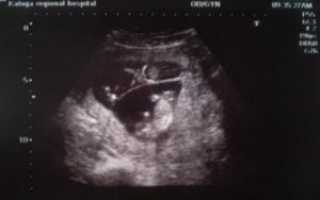

Увидеть двойняшек на мониторе при ультразвуке можно начиная с самых ранних сроков. В это время малыши только-только начинают оформляться, и на экране видно просто 2 темных пятнышка. Но у каждого из них уже есть маленькое сердечко, которое вполне реально услышать.

Если будущая мама впервые узнала о двойняшках на первом плановом ультразвуке в 9-11 недель, она может увидеть полноценных эмбрионов длиной в 4,5-4,8 см.

Первое узи. Беременность двойней 5 недель. Первый триместрПервое узи. Беременность двойней 5 недель. Первый триместр

Следовательно, наличие двойняшек в утробе выявляется посредством ультразвука уже через месяц после зачатия, на снимке они выглядят как 2 образования темного цвета внутри полости матки (см. фото УЗИ-обследования двойни ниже).

Увидеть двойню на УЗИ при беременности можно уже через месяц после зачатия. В этом случае специалист отметит на экране монитора два пятна черного цвета, которые хорошо просматриваются ультразвуком